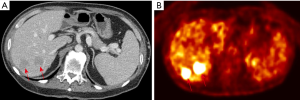

A 49-year-old male reported to the hospital with multiple and various sizes of hypoechoic nodules in the right lobe of the liver during regular follow-up ultrasound surveillance after the operation. He had a personal history of ascending colon cancer and underwent right hemicolectomy half a year ago. The laboratory results of serum carbohydrate antigen-199 (2.7 ng/mL) and carcinoembryonic antigen (1.2 ng/mL) were all within normal limits. The other biochemical tests were nonspecific. Due to the findings of multiple hepatic nodules, subsequent CT examination was performed and demonstrated multiple, low attenuating nodules measuring 20–45 mm in size in S4–8 of the liver, no early enhancement in the arterial phase but slight peripheral enhancement in the portal venous phase (Figure 1A) after the administration of intravenous contrast agent. Fluorine-18 fluorodeoxyglucose positron emission tomography/CT (F-18 FDG PET-CT) revealed hepatic nodules are hypermetabolic (Figure 1B), highly suspecting metastases in the right lobe of the liver, considering personal colon cancer history. The patient received an ultrasound-guided fine needle biopsy (FNA) for tissue proof. Histopathological findings revealed granulomas with Langhans giant cells and infiltration of epithelioid and inflammatory cells, and the final diagnosis was a chronic inflammatory granuloma, while Ziehl-Neelsen staining and acid-Schiff staining showed negative for acid-fast bacilli and fungi. The polymerase chain reaction (PCR) for formalin-fixed paraffin-embedded tissue revealed NTM infection. The follow-up CT examination after three months showed no significant changes in previous hepatic granuloma and no newly appeared lesions.